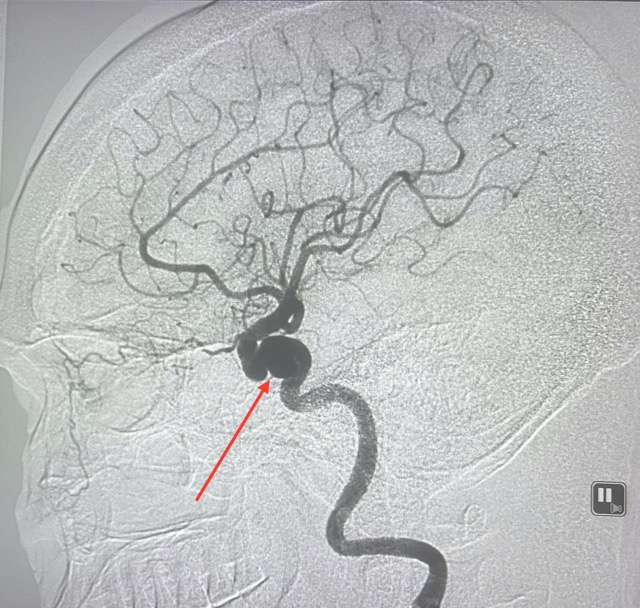

Saving a patient with a giant aneurysm in the brain

Thong Nhat Hospital and Le Van Thinh Hospital have just coordinated to promptly save the lives of two patients with brain aneurysms as big as eggs.